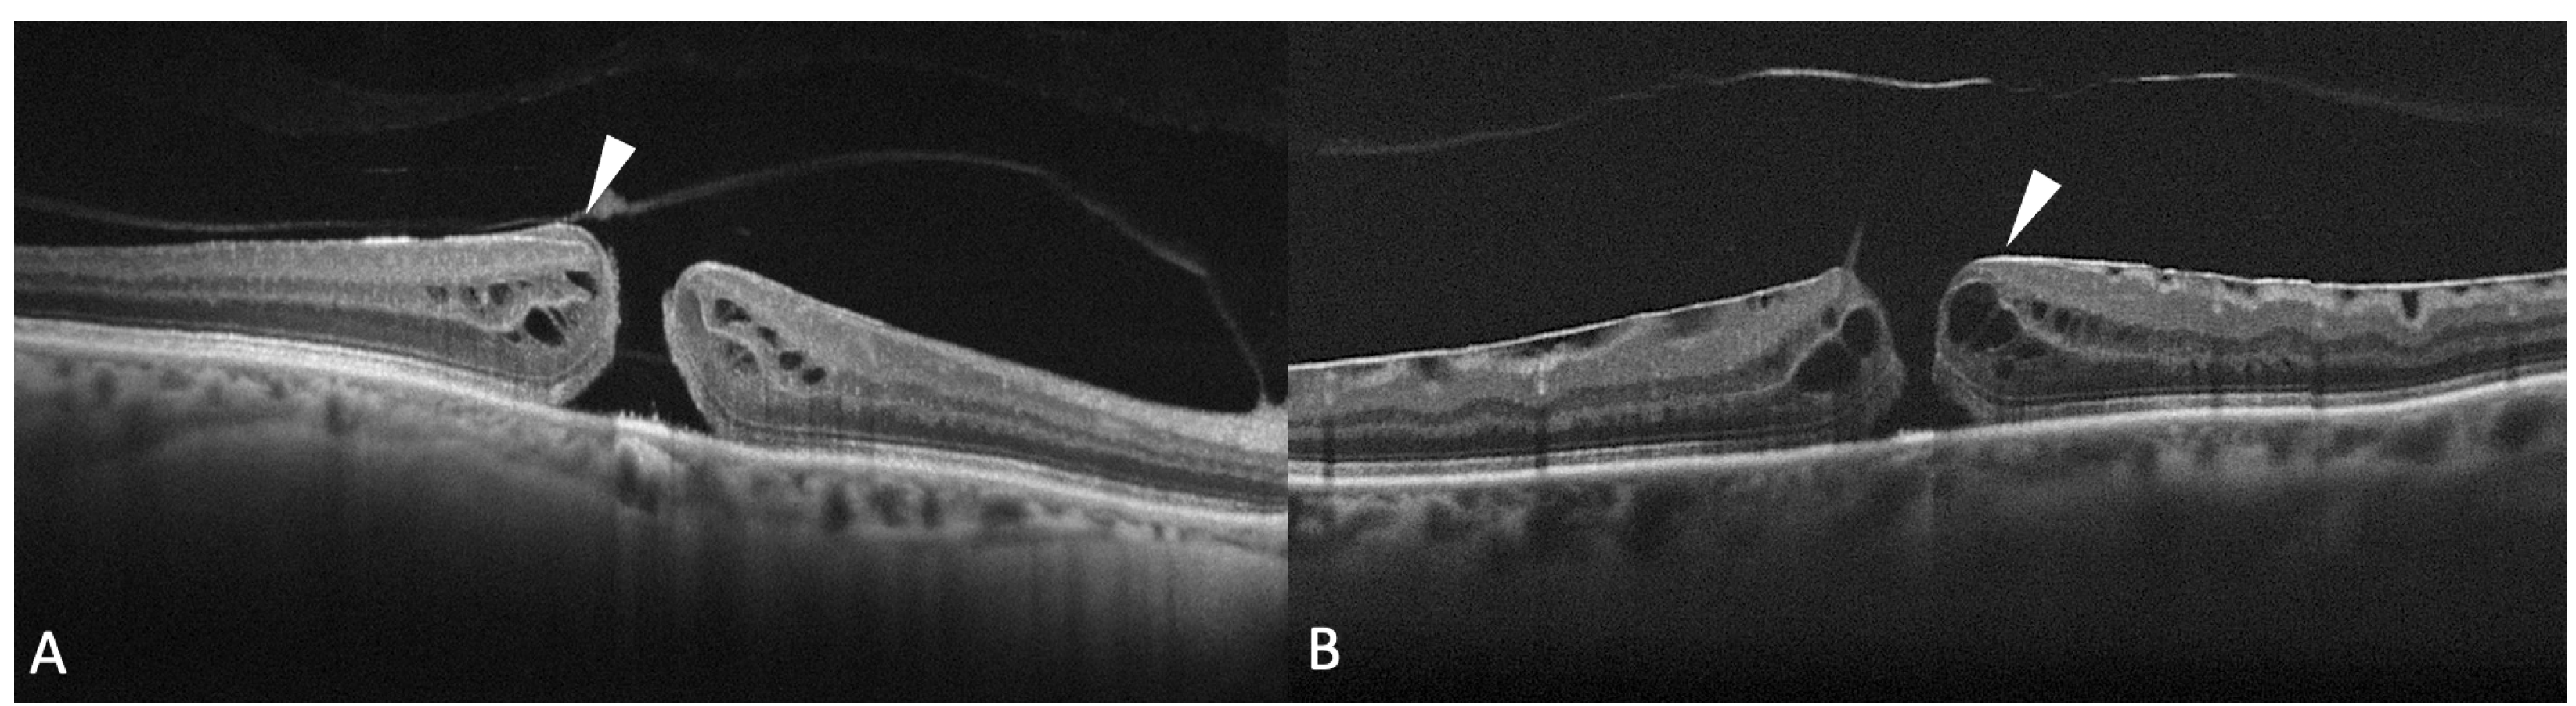

It has been reported that FTHM can be associated with the presence of epiretinal proliferation, also known as atypical epiretinal tissue, identified in structural OCT. Epiretinal proliferation presents as a premacular tissue with homogenous medium reflectivity over the internal limiting membrane on OCT and it is distinct from a hyperreflective tractional epiretinal membrane (Figure 5). Although it is most frequently associated with a lamellar hole, some cases of FTMH also show atypical epiretinal tissue at the edge of the hole. FTMHs with epiretinal proliferation have been reported to have worse clinical and surgical outcomes than FTMH without it [43]. The imaging and histopathological findings imply that the development of FTMH with epiretinal proliferation may not be reconducted to vitreomacular traction. Instead, FTMH with atypical epiretinal tissue might have evolved from lamellar holes with atypical epiretinal tissue. Bae et al. also explored the presence of atypical epiretinal tissue in FTMHs and its pathogenic and prognostic significance [44]. The authors studied 225 consecutive eyes of 211 patients who underwent surgery for an idiopathic FTMH. Eyes were divided into two groups according to the presence of epiretinal proliferation. It was found in 11.6% of the eyes. At baseline, eyes with atypical epiretinal tissue more frequently had a splitting of the inner retina but fewer intact photoreceptors compared with eyes without it. The presence of atypical epiretinal tissue was associated with moderately poorer outcomes at 12 months after surgical treatment, probably due to a large number of defects in the ELM, EZ, and IZ observed postoperatively. So, the authors hypothesized that the presence of epiretinal proliferation in an FTMH was related to poorer anatomical success and less visual recovery after surgery, suggesting that it reflects a chronic pathogenic process involving more severe damage to the foveal tissue. Ishida et al. evaluated the presence of preretinal abnormal tissue (atypical epiretinal tissue, perivascular glia, and a preretinal hyperreflective band) in a study on 60 eyes with FTMH, finding it in most eyes (94%) [45]. In 24%, the abnormal tissue was contiguous to the hole. In the others, it was extrafoveal. Eyes with preretinal tissue contiguous to the FTMH had worse baseline VA.

Figure 5.

(A) Optical coherence tomography (OCT) scan showing a full-thickness macular hole (FTMH) accompanied by atypical epiretinal tissue (arrowhead); (B) OCT scans showing a hyperreflective epiretinal membrane associated with FTMH (arrowhead).